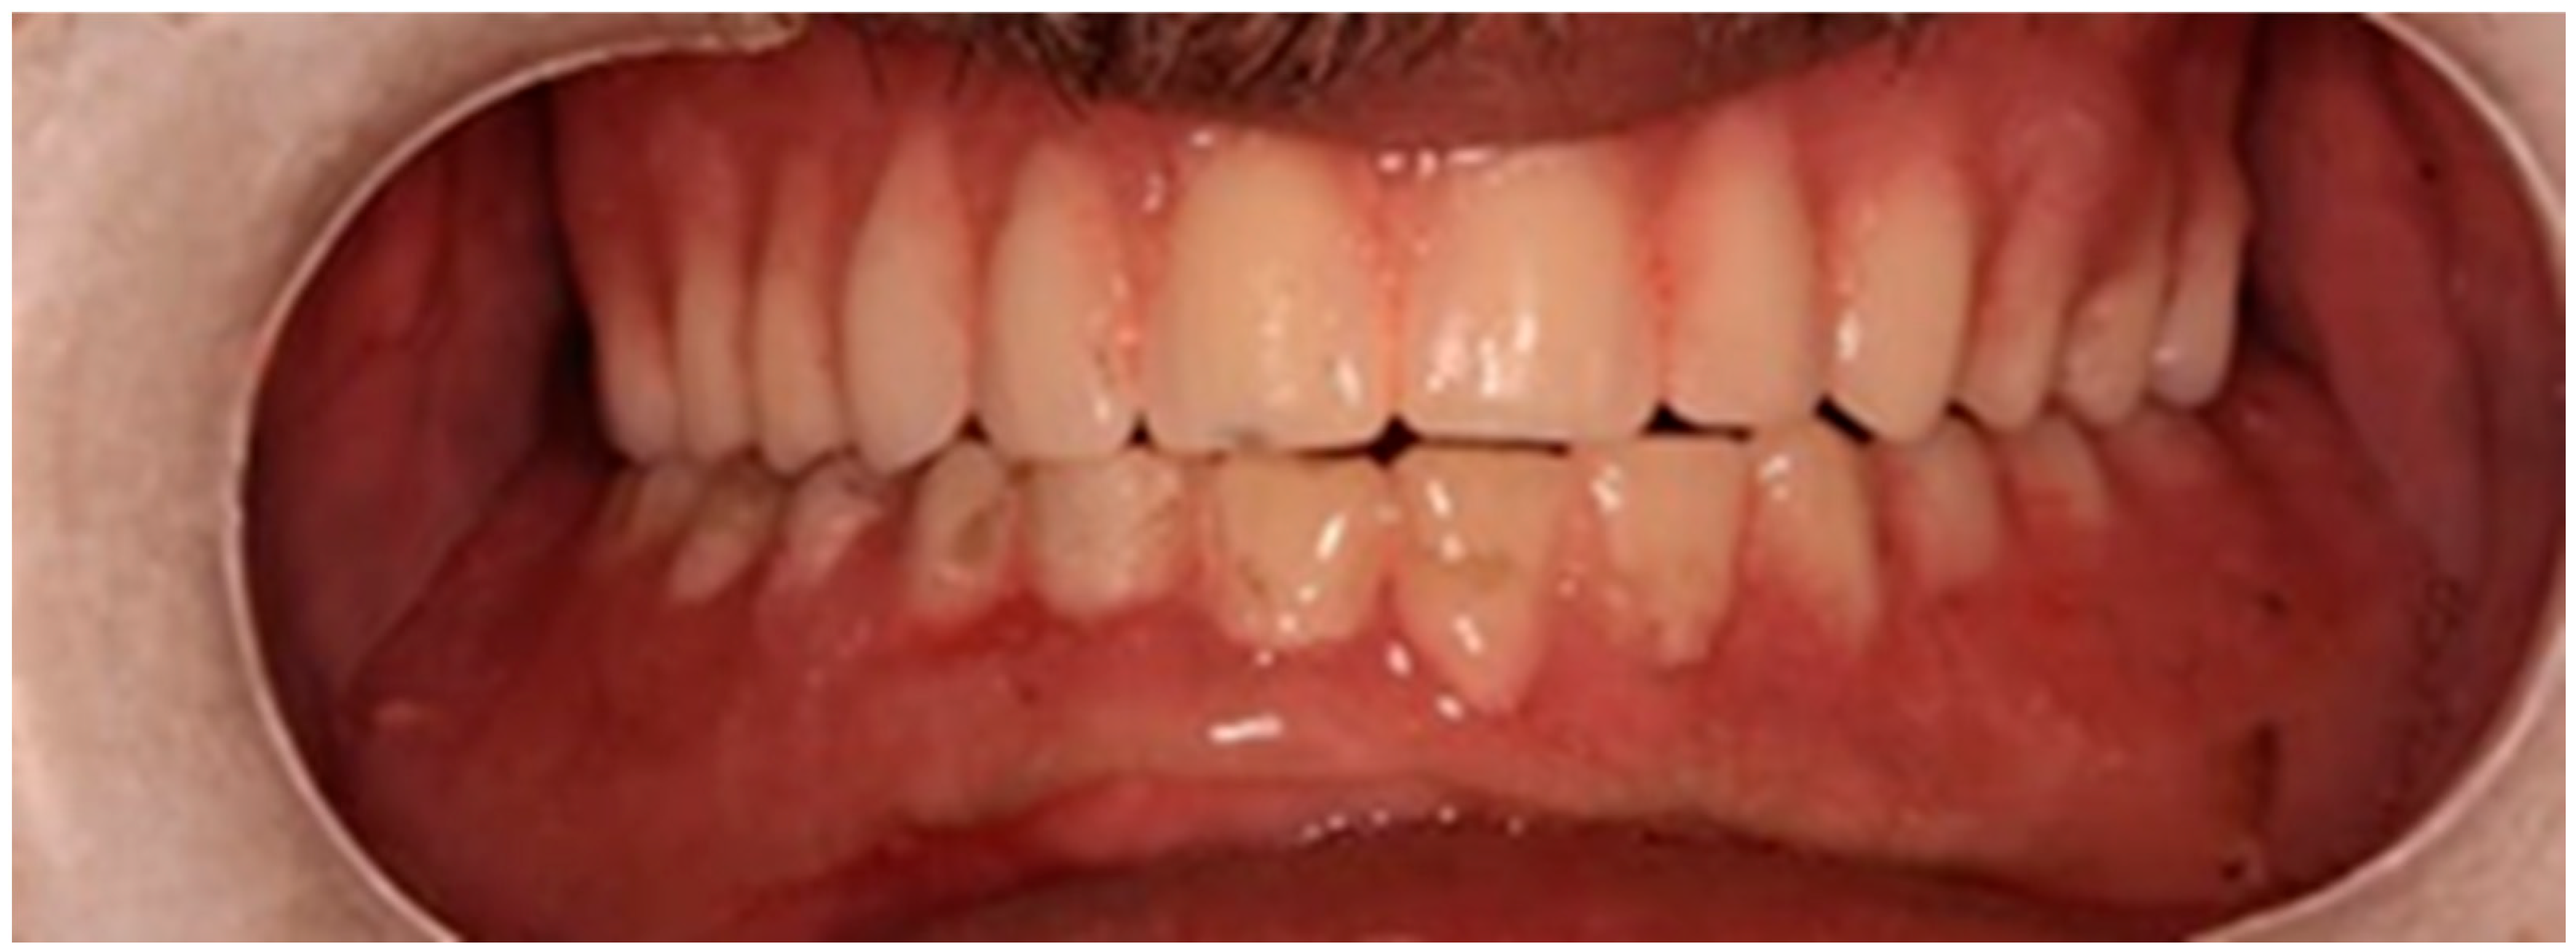

2.2. Second Visit

The edentulous spaces in the lower partial denture were then restored to replace the extracted teeth. The existing upper denture was positioned with the lower denture to re-evaluate the vertical dimension, aesthetics, and phonetics (Figure 3).

Figure 3. Image showing the upper and lower dentures.